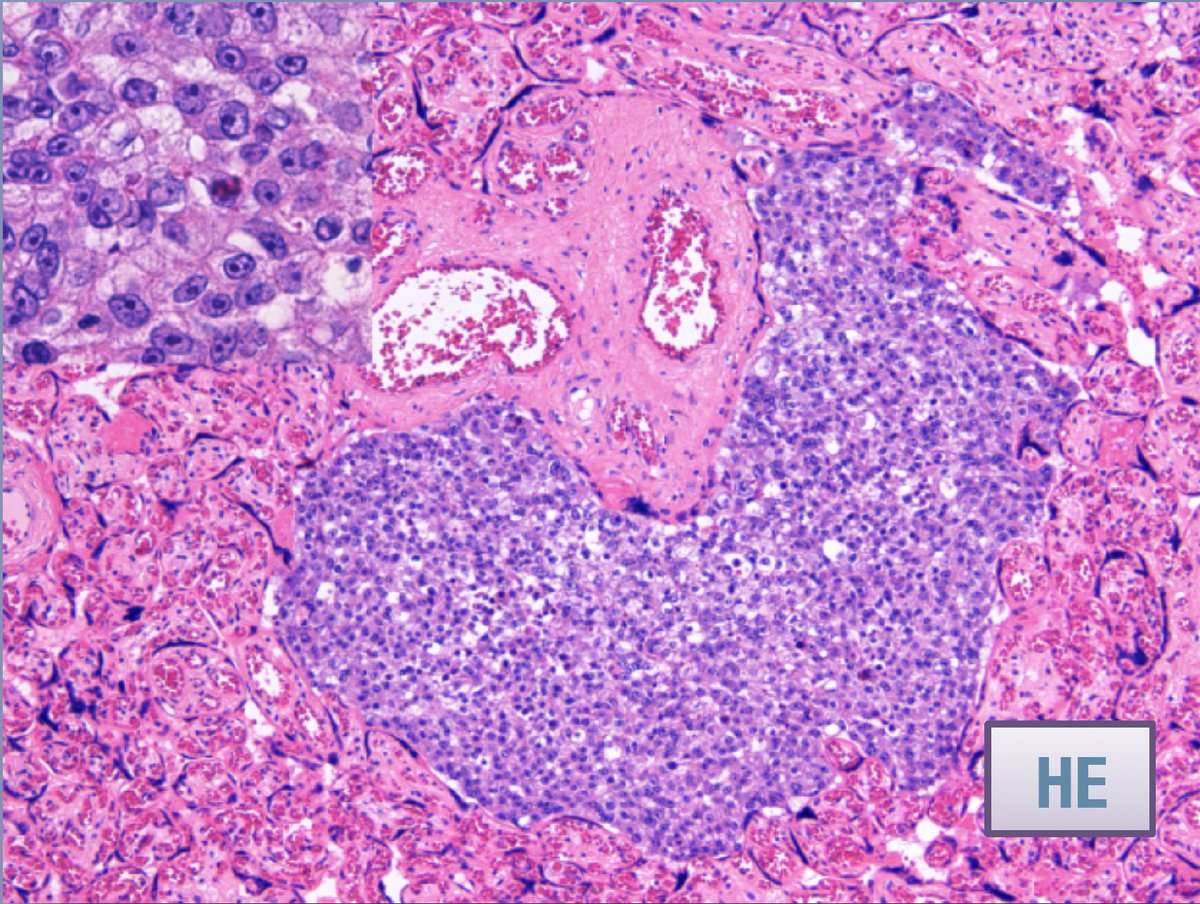

📢Test your knowledge with our Case of the Week! from docs @Hopitaux_unige Young woman, 37 weeks gestation presents with newly diagnosed, widely metastatic non-small cell lung cancer. Metastases to this organ could lead to increased risk for the newborn. Which organ is it?